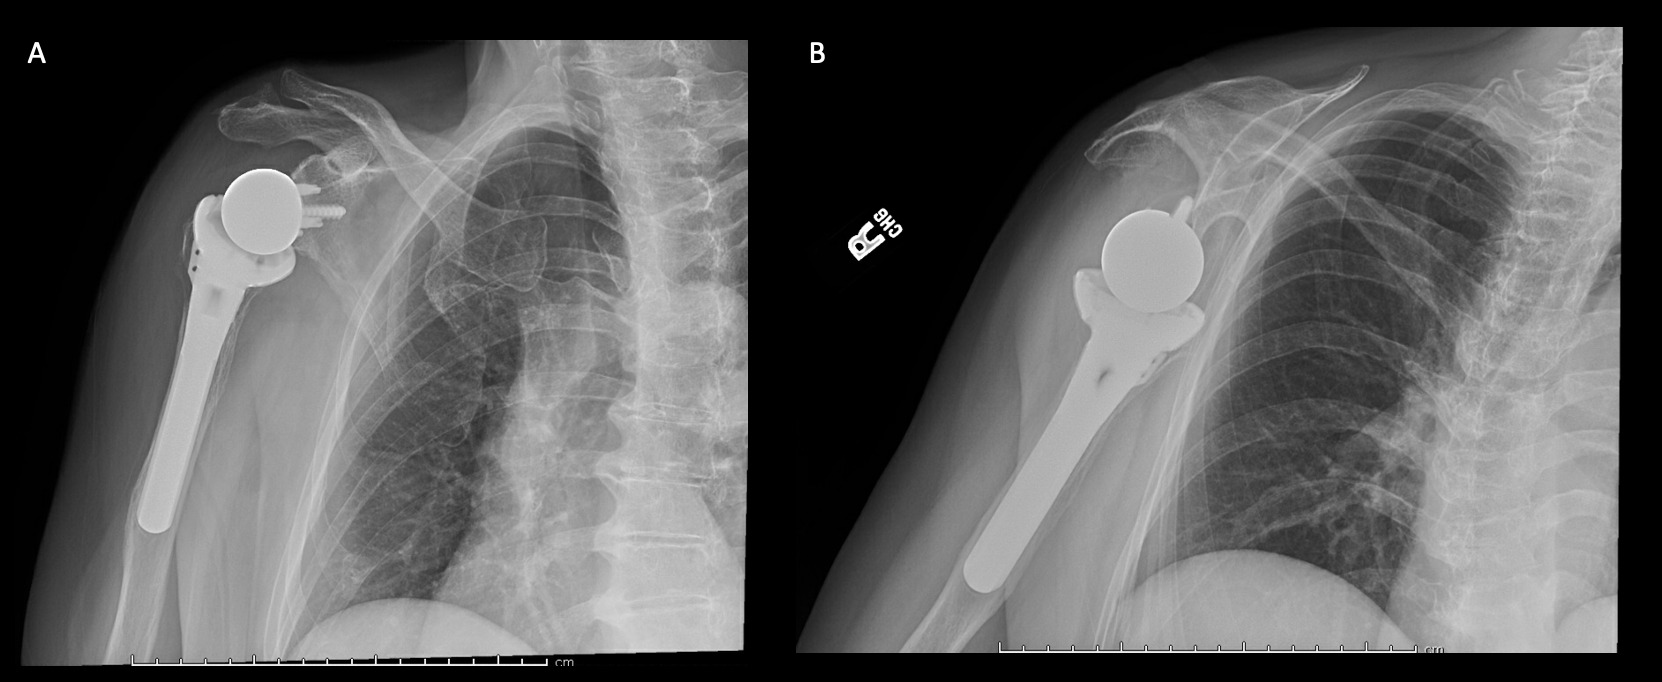

Case 1. At the latest follow-up one-year post-op, patient 1, who had the more extensive humeral exposure, was extremely pleased with the results of the surgery despite occasional pain. She had resolution of an early post-op radial nerve palsy. She could button up her blouse and get her hand to her mouth. Her shoulder and scapular x-rays showed some new radiolucency between the superior aspect of the glenoid prosthetic component and the associated bone cement in the subacromial space (Figure 13). At 2 years post-op she continues to have significant pain relief and has maintained her active range of motion (AROM). Elbow AROM was from 10 to 145 degrees. Shoulder AROM was abduction to 15 degrees and internal rotation allowing the hand to reach the level of L5/S1 vertebrae.

Case 2. At the latest follow-up one-year post-op, the patient expressed that the pre-operative pain had resolved after the operation. Despite this, she stated that if given the option again she would not undergo the surgery because she did not attain the function she expected and felt that her function may have decreased compared to pre-op. Overall stability and alignment were good. On physical exam, she was able to reach within 1 inch from her mouth and had 20 degrees abduction and 5 degrees forward flexion actively. Active elbow flexion was 0 to 120 degrees (Figures 14). At 2 years post-op she had some regression in her pain but accompanied by modestly decreased AROM. Shoulder AROM was 15 degrees abduction, and 5 degrees forward flexion. Elbow AROM was from 0 to 105 degrees of elbow flexion. CT scan showed increased lucency surrounding the humeral component concerning for osteolysis and prosthesis loosening (Figure 14). Blood work at the 2-year mark to investigate the radiolucencies and decreased AROM left us with low suspicion for infection (WBC 5.4, ESR 33, CRP <3.0).